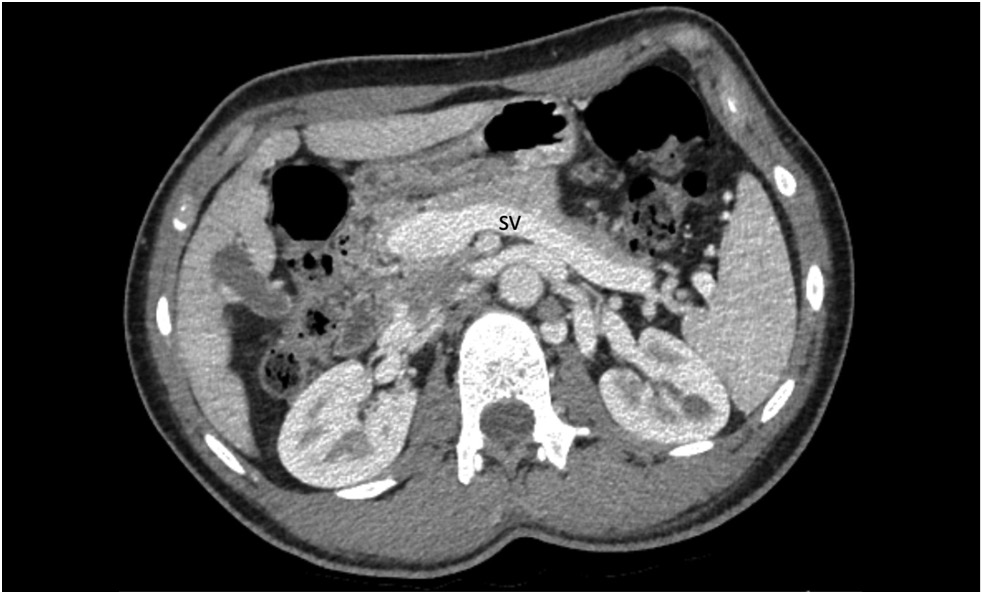

Contrast-enhanced abdominal computed tomography (CT) with multiplanar reconstruction revealed that the splenic (12 mm in diameter (Figure 1)) and superior mesenteric veins fused together, forming a portal vein conduit dilated to 28 mm in diameter (Figures 2 and 3), flowing directly into the inferior vena cava (IVC), bypassing the porta hepatis (Figure 4). Moreover, moderate liver and spleen enlargement and weak heterogeneous contrast enhancement of the liver parenchyma were noted. The findings were consistent with Abernethy malformation type Ib.

Fig. 2. Contrast-enhanced CT, portal phase, coronal view. Splenic (SV) and superior mesenteric (SMV) veins fused together, forming a portal vein conduit (white arrow).